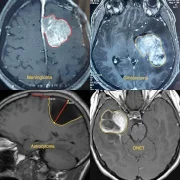

At our advanced Neurosurgery Center in Thane, we specialize in brain tumor surgery with a focus on both complete tumor removal and the preservation of neurological functions. Using modern techniques such as microsurgery, endoscopic brain surgery, and neuronavigation systems, our neurosurgeons ensure safe and precise treatment. Whether it is a glioma, meningioma, pituitary tumor, or metastatic brain tumor, we provide personalized surgical care for the best outcomes. Patients benefit from shorter hospital stays, faster recovery, and improved quality of life after surgery.

– Brain Tumors

– Cerebrovascular Diseases

– Pediatric Brain Tumors

– Skullbase Tumors

– Ventricular Brain Tumors